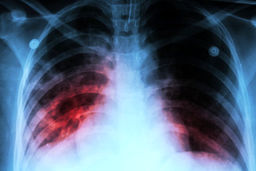

سل

افزایش مرگ و میر جهانی سل برای اولین بار در ۱۵ سال گذشته

خبرمهم: سازمان جهانی بهداشت (WHO) در یک گزارش جدید اعلام کرد که برای اولین بار در ۱۵ سال گذشته، مرگ و میر جهانی سل در…